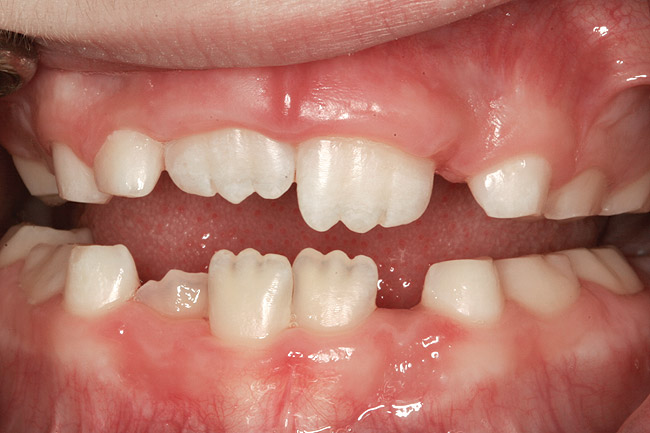

(10.) Narrow maxilla with tooth wear and bilateral crossbite.

Figure 10

(12.) Class II Angle classification with worn dentition and anterior open bite.

Figure 12